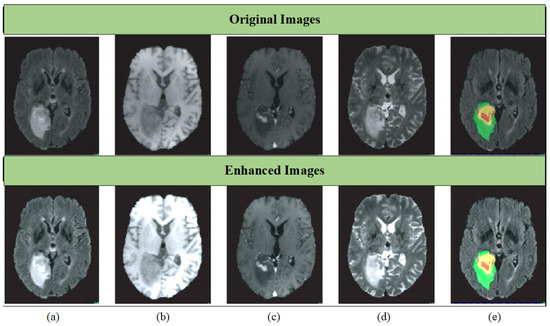

3.1. Data Pre-Processing

4.6. Qualitative Analysis